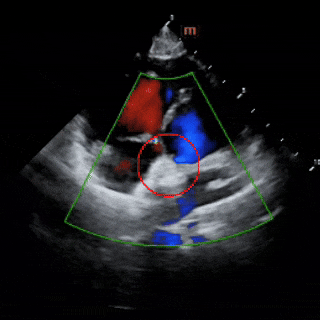

锁定后评估

彩色多普勒血流成像显示无残余分流存在

释放后评估

超声下可见封堵器形态良好,多普勒显示无残余分流,封堵成功。

出院前评估

超声所见:1、各房室腔内径正常。大动脉内径及位置关系正常。2、室间隔及左室后壁厚度及运动幅度正常。房间隔中部见封堵器回声,位置良好,CDFI:房水平未见明显分流。室间隔连续。3、CDFI示三尖瓣见小反流束;余瓣膜形态回声及启闭未见明显异常。4、心包厚度正常,心包腔内未见液性暗区。5、心功能测值正常。

超声提示:房间隔封堵器术后,封堵器位置正常。

出院前患儿心功能指标正常,肺动脉压恢复正常,二尖瓣反流消失,三尖瓣反流由术前少量转为轻微。